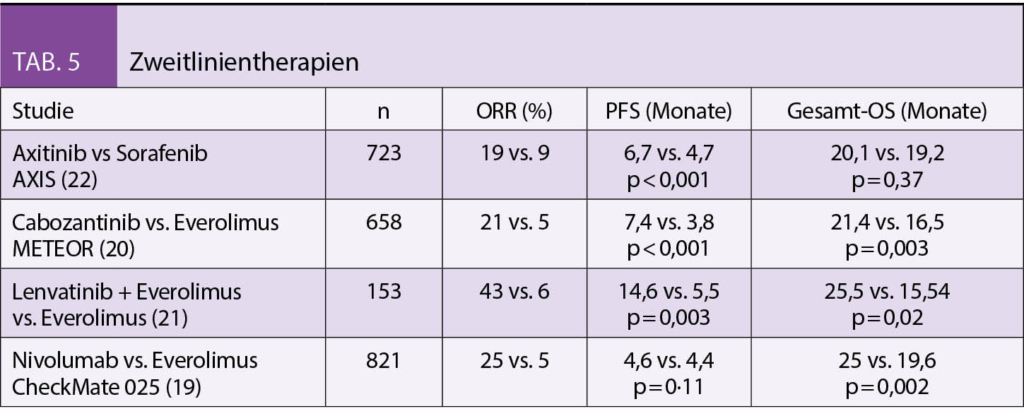

Viele Medikamente der Erstlinie sind auch in der Zweitlinie wirksam. Der Einsatz der Medikamente ist abhängig von der Art der Vorbehandlung und dem Allgemeinzustand des Patienten. Hat ein Patient in der Erstlinie ein TKI kann in der Zweitlinie entweder eine Monotherapie mit dem Immuncheckpointinhibitor Nivolumab (CHECKMATE- 025) oder eine erneute Therapie mit einem anderen TKI, z.B. mit Cabozantinib (METEOR Studie) überlegt werden (19-20). Beide Substanzen hatten in den Zulassungsstudien gegenüber dem damaligen Standard Everolimus, einem mTOR-Inhibitor, einen signifikanten PFS und OS Vorteil gezeigt. Eine weitere Alternative mit einem signifikanten Vorteil im Tumoransprechen und PFS ist die in einer Phase-II Studie getestete Kombination mit dem TKI Lenvatinib in Kombination mit Everolimus. (21) Auch Axitinib ist für die Zweitlinie bei nachgewiesenem signifikantem PFS Vorteil gegenüber dem TKI Sorafenib zugelassen (22). Eine TKI Therapie sollte in jedem Fall bei Patienten eingesetzt werden, die initial mittels einer Immuncheckpointkombination behandelt wurden. Auch bei Patienten, die zunächst mit der Kombination aus Axitinib/Pembrolizumab therapiert wurden ist der Einsatz von Cabozantinib, einem anderen TKI oder der Kombination Lenvatinib/Everolimus indiziert. Eine Kombinationstherapie mit Nivolumab/Ipilimumab kann prinzipiell als Zweitlinientherapie evaluiert werden sofern nicht bereits in der Erstlinie appliziert. Daten zu diesem Vorgehen gibt es derzeit jedoch nicht (Tab. 5).